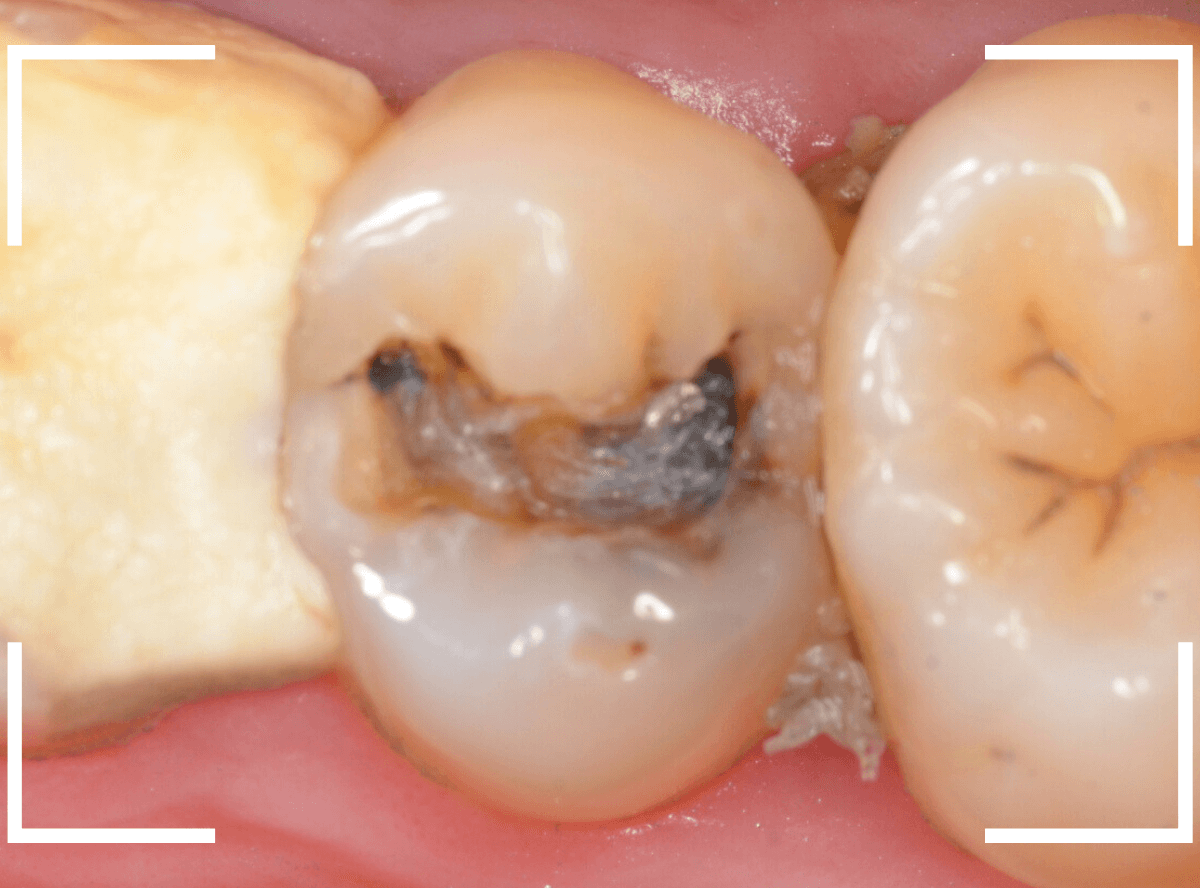

Case.23 歯のすきまから両側が大きな虫歯

「下の奥歯が痛む」という訴えで来院された患者さんのケースです。

目視でも、手前の奥歯がかけていて、中で虫歯が広がってるであろうことは予想できます。

ピンセットで歯を叩いてみても、手前の奥歯が痛むようです。

レントゲン写真で確認します。

青い線が神経、赤い線が虫歯の範囲です。

奥歯の方がより深い虫歯に見えますが、再度打診で確認したところ、やはり手前の奥歯が痛むそうです。

状況から、まず手前の奥歯から治療となりました。

麻酔をして、手前の奥歯のレジンを慎重に外します。

前に虫歯の治療をした時点で、神経スレスレの状態でしたので、削りすぎないように慎重にレジンを外さなければいけません。

レジンを外して、う蝕検知液で確認します。

レジンの中で虫歯が進行していたのがわかります。

慎重に全ての虫歯を除去しました。

何とか、神経が露出せずに済んでいます。

お薬をつめて、セメントで蓋をして経過観察します。

後日、状況を確認したところ、虫歯処置した後も、手前の奥歯が痛むとの事でした。

「我慢できないほどでもない」との事でしたので、引き続き経過観察しつつ、奥歯の治療を治療する事になりました。

奥歯は、レントゲンで見た通り、少し歯を削るとすぐに虫歯の穴が出てきました。

こちらは、ある程度虫歯を取ったところで染め出してみると真っ赤です。

ですが、何とか神経に達する前に、全ての虫歯を除去できました。

神経の治療が必要かと思っていたので、その点は幸運でした。

奥歯もお薬をつめて、セメントで蓋をして経過観察です。

何とか神経を取らずに済ませたいですが、どうなる事か・・・。